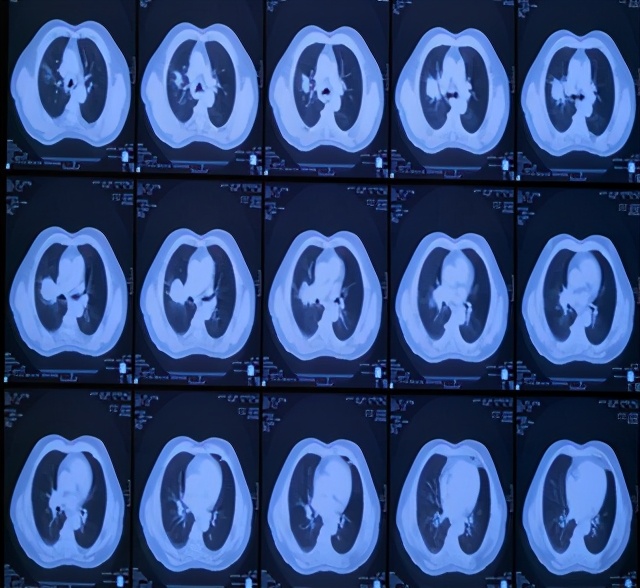

治疗后5年复查,患者偶有咳血,局部病灶纤维化改变

治疗后11年复查,无明显活动后 气喘 。